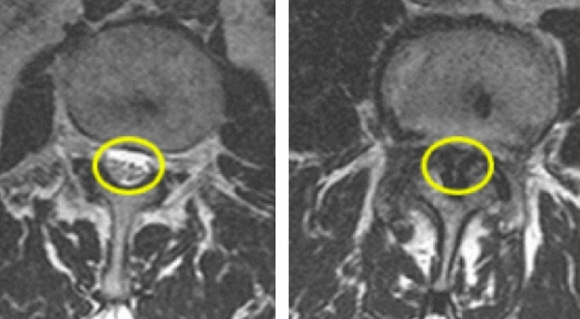

▲정상 척추(좌)와 척추관협착증 환자의 척추(우) 모습. 오른쪽 사진의 표시 부위를 보면 두꺼워진 인대(검은 부분)와 관절을 확인할 수 있다.

척추관협착증은 척추관이 선천적으로 좁아서 발생하는 경우도 있으나 대부분 척추 주변의 관절이나 인대가 두꺼워지고 디스크의 퇴행성 변화로 인해 신경을 압박하는 것이 주된 원인이다.